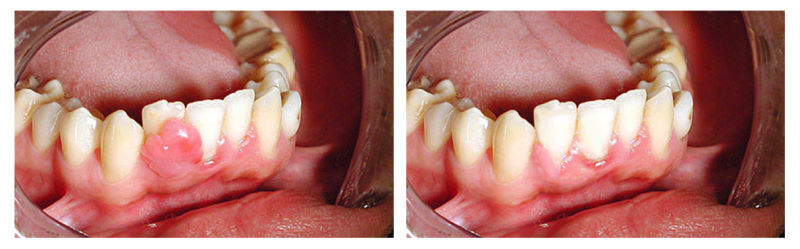

Киста на десне: фото до и после